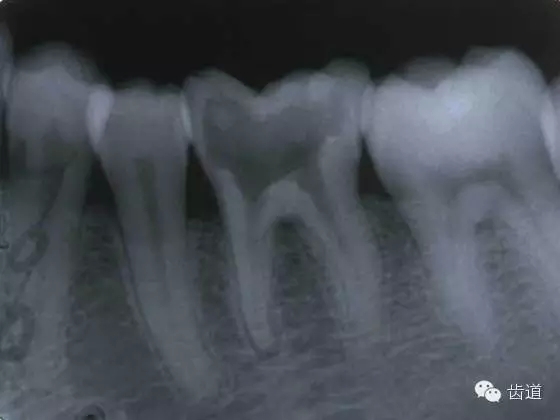

(3)髓室底穿孔:處理方法同上。同時(shí)找到根管口,按常規(guī)進(jìn)行根管預(yù)備和充填。如穿孔范圍太大易導(dǎo)致根分歧病變,予后欠佳??尚懈芡饪啤?/span> (4)根管壁形成臺(tái)階:先換小號(hào)銼去除臺(tái)階,再順序擴(kuò)挫。如根管壁穿孔,找到主根管進(jìn)行預(yù)備后,主根管及側(cè)穿道同時(shí)充填。在根尖1/3或根尖彎曲處側(cè)穿,根充后,配合根尖手術(shù)——根切+倒充填。 (三)髓腔壁穿孔的預(yù)防 1.掌握每個(gè)牙齒的髓腔解剖形態(tài)及其在牙齒表面的投影范圍。 2.術(shù)前拍X線片。 3.進(jìn)行規(guī)范化操作,隨時(shí)與X線片核對(duì)器械進(jìn)入方向及進(jìn)入深度。 器械折斷在根管內(nèi),阻塞根管,妨礙治療操作。如不能取出,使根管治療不能繼續(xù)進(jìn)行,不得不輔以根尖手術(shù)。 左上7近中頰根器械折斷 右上6腭根器械折斷 1.器械本身的原因 材料質(zhì)量欠佳,受力后易折斷。 器械反復(fù)使用,產(chǎn)生折痕,用力后也易折斷。 消毒方法不當(dāng),消毒液中未放防銹劑,器械銹蝕易折。 2.術(shù)者器械使用不當(dāng) 遇有阻力,仍強(qiáng)行進(jìn)入,用力過(guò)大過(guò)猛,超過(guò)了器械所能承受的程度 未按操作要求使用器械(跳號(hào)) 器械在細(xì)窄根管內(nèi)被卡住后,仍勉強(qiáng)旋轉(zhuǎn)器械柄 折斷于根管內(nèi)的器械要盡量取出,若無(wú)法取出經(jīng)常規(guī)充填后,成功率不受明顯影響。 1.折斷器械有一部分露在根管口外,用鑷子或持針器夾取出。 2.器械斷端在根管口內(nèi):用超聲根管銼在該器械旁增隙,通過(guò)超聲震蕩和沖洗,可將折斷器械從根管內(nèi)震動(dòng)沖出。在手術(shù)顯微鏡下直視操作,大大提高了取出的成功率。 3.折斷器械尖端已超出根尖孔:無(wú)癥狀不處理;有疼痛則作根尖手術(shù)取出。 4.折斷器械較長(zhǎng),各種方法均不能取出,可作根管電解消毒,塑化治療或塑化劑處理,根管充填。 若患牙根尖有病變,必要時(shí)作根尖切除+倒充填。 1.使用前認(rèn)真檢查器械有無(wú)生銹、折痕、螺紋松解等現(xiàn)象。 2.嚴(yán)格按器械使用規(guī)則進(jìn)行操作。 3.使用機(jī)用根管器械,應(yīng)支點(diǎn)穩(wěn)、轉(zhuǎn)速慢,并只能應(yīng)用于直的根管。 4.制備開(kāi)髓洞形時(shí),應(yīng)充分暴露根管口,對(duì)彎曲根管能盡量減少其彎曲度,對(duì)彎曲度在30o以上的根管盡量采用超聲根管預(yù)備并使用鎳鈦根管挫。 5.控制器械使用次數(shù):根管銼刃部的鋒利程度隨所預(yù)備的根管數(shù)目增加而降低。 25#以下器械只能用1—2次,30#—50#器械可用二次。 牙折分為冠折、根折及冠根折三種。根管治療后,由于牙折導(dǎo)致拔除者屢見(jiàn),故應(yīng)引起足夠重視。 (一)牙折發(fā)生原因 1.經(jīng)根管治療的牙齒,因失去了牙髓的營(yíng)養(yǎng)而脆性增大。 2.制備開(kāi)髓洞形時(shí),過(guò)多的磨除了牙體組織,削弱了牙體組織強(qiáng)度。 3.根管清理和成形以及做冠樁預(yù)備過(guò)程中,過(guò)多的磨除根管壁,削弱了牙根強(qiáng)度。 4.用牙膠做根管充填時(shí),側(cè)向或垂直壓力過(guò)大,均可造成牙根縱折。 5.其他:根管釘、樁的采用;熱塑冷凝的牙膠尖填入根管后自身體積膨脹;牙周受累的牙齒,支持骨喪失,也增加了牙折的機(jī)會(huì)。 (二)牙折的處理 應(yīng)盡可能保存患牙 1.冠折:根據(jù)折斷的牙體組織的多少及部位,可分別選擇充填;加螺旋釘固位;全冠或樁冠修復(fù)。 2.冠根折:折斷線在齦下不足3mm,配合齦切術(shù)或冠延長(zhǎng)術(shù),將斷端暴露在齦上,然后根據(jù)缺損情況考慮冠修復(fù)的種類。 折斷線在齦下超過(guò)3mm,患牙牙根較長(zhǎng),正畸力將牙根牽引,無(wú)條件做正畸治療的單根牙則拔除,多根牙則可做截根或半切除術(shù)。 3.根橫折:在冠方1/3處理方法同冠根折。 在根中1/3根折線不與牙周袋相通,做根內(nèi)固定,加牙冠部夾板固定4—8周。在根尖1/3,調(diào)合 解除創(chuàng)傷力,如有癥狀做根尖切除術(shù)。 4.根縱折:?jiǎn)胃绖t拔除;多根牙做截根術(shù)或半切除術(shù)。也有報(bào)告,用切開(kāi)翻瓣暴露縱折牙根,粘接劑粘合裂根的方法保留縱折牙牙根,若以后出現(xiàn)牙周袋則拔除。 (三)牙折的預(yù)防 1.根管治療過(guò)程中,有薄壁銳尖或陡峭的無(wú)基釉質(zhì),應(yīng)及時(shí)降低咬合或磨除。根管治療后,常規(guī)調(diào)合。 2.根管治療應(yīng)遵循:在保證治療的前提下,盡量保留健康的牙體組織。 3.根管充填操作用力適度。 五、下唇麻木 (一)發(fā)生原因:主要由下齒槽神經(jīng)損傷所致 1.治療操作中藥物、器械或根充物超出根尖孔,進(jìn)入下頜管損傷下齒槽神經(jīng) 2.解剖因素:下頜牙齒根尖距下頜管太近,有些牙根與下頜管相連,以下頜第二恒磨牙多見(jiàn) 左下7根充后下唇麻木 左下5根管預(yù)備后下唇麻木 (二)處理: 1.根據(jù)病史認(rèn)真查找原因,如為炎癥刺激所致,應(yīng)積極治療根尖周炎,加口服營(yíng)養(yǎng)神經(jīng)藥物。 2.理化刺激所致,口服營(yíng)養(yǎng)神經(jīng)藥物。 (三)預(yù)防: 1.作根管治療前拍X線片,下頜牙齒應(yīng)特別注意與下頜管的關(guān)系。 2.準(zhǔn)確測(cè)量根管工作長(zhǎng)度,各種操作均在工作長(zhǎng)度范圍內(nèi)進(jìn)行。根管封藥不可過(guò)飽和,防止藥液溢出根尖孔。 此種意外發(fā)生,給患者帶來(lái)很大的精神壓力,如器械落入呼吸道,則增加更大的痛苦,應(yīng)慎重處理。 (一)發(fā)生原因 1.術(shù)者精神不集中 2.患者過(guò)于緊張不合作 3.患者體位不正確 4.器械從手中滑脫 (二)處理 1.醫(yī)護(hù)人員應(yīng)鎮(zhèn)靜,安撫患者。 2.立即拍腹部平片。 3.落入消化道應(yīng)住院觀察。 4.服用長(zhǎng)纖維及有潤(rùn)滑作用的食物,勿服瀉藥。 5.適當(dāng)走動(dòng),勿劇烈運(yùn)動(dòng)。 6.每天拍腹部X線片,檢查大便至排出。 7.落入呼吸道,應(yīng)請(qǐng)耳鼻喉科或胸外科醫(yī)生協(xié)助取出。 (三)預(yù)防: 1.針對(duì)原因預(yù)防。 2.治療時(shí)上橡皮障。 3.無(wú)條件用橡皮障,可在器械柄拴安全鏈。 皮下氣腫是根管治療中少見(jiàn)的并發(fā)癥 (一)臨床表現(xiàn) 根據(jù)患牙的部位不同,可分別出現(xiàn)在頰部、頸部、和眶周等疏松軟組織迅速腫脹、充血,有捻發(fā)音。捻發(fā)音是組織氣腫的病理特征,以此和其他腫脹做鑒別。如空氣向頸部移動(dòng)可引起呼吸困難。 (二)發(fā)生原因 1.用壓縮空氣吹干根管時(shí)間過(guò)長(zhǎng)。 2.使用過(guò)氧化氫液沖洗根管,將藥液壓出根尖孔。 不可加壓??! (三)處理 一般不需特殊治療,給予抗生素預(yù)防感染 上頜竇曲霉病、上頜竇疼痛、上頜竇炎癥等。 根管治療的各種并發(fā)癥,絕大多數(shù)情況是由術(shù)者操作不規(guī)范所致。在根管治療過(guò)程中,術(shù)者應(yīng)嚴(yán)格按照規(guī)程進(jìn)行每一步操作,這些并發(fā)癥是完全可以避免的。